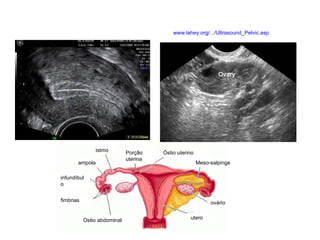

Sistema Reprodutor Ógãos que produzem, transportam e armazenam células germinativas Testículos  e ovários produzem células germinativas maduras.  Órgãos de transporte e armazenamento Homem: Ducto deferente,  próstata e  pênis Mulher: útero,  trompas uterinas e  vagina

www.lahey.org/.../Ultrasound_Pelvic.asp istmo ampola Porção uterina infundíbulo fimbrias Ostio abdominal utero ovário Meso-salpinge Óstio uterino

Trompa Trompa pérvia – extravasamento do contraste injetado Cânula www.uptodateonline.com/patients/content/topic...

Sistema Reprodutor Ógãosque produzem, transportam e armazenam células germinativas Testículos e ovários produzem células germinativas maduras. Órgãos de transporte e armazenamento Homem: Ducto deferente, próstata e pênis Mulher: útero, trompas uterinas e vagina

www.lahey.org/.../Ultrasound_Pelvic.asp istmo ampolaPorção uterina infundíbulo fimbrias Ostio abdominal utero ovário Meso-salpinge Óstio uterino

Trompa Trompa pérvia– extravasamento do contraste injetado Cânula www.uptodateonline.com/patients/content/topic...